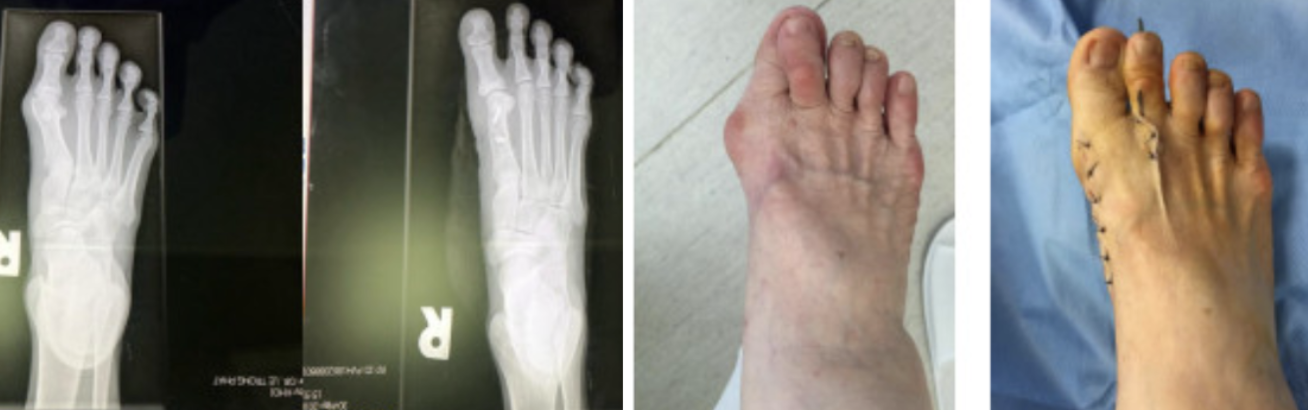

Ngón chân cái vẹo (ảnh chụp trước và sau phẫu thuật).

Theo TS.BS Lê Trọng Phát, căn bệnh ngón chân cái vẹo ngoài hiện nay chưa được quan tâm đúng mức. Nhiều bệnh nhân tới khám khi đã có cơn đau viêm khớp ngón cái. Ít người tìm tới bác sĩ khi chân cái bất thường và chưa có triệu chứng đau.

“Trường hợp nặng, người bệnh được chỉ định phẫu thuật. Mục tiêu của phẫu thuật là chỉnh trục xương và phần mềm (gân, cơ)", bác sĩ Phát cho biết.

Việc điều trị các bệnh lý ở bàn chân đòi hỏi sự tỉ mỉ và kinh nghiệm của các chuyên gia. Trên thế giới có hơn 130 phương pháp phẫu thuật điều trị bệnh này, trong đó 3 phương pháp phẫu thuật Chevron, Lapidus và Scarf được đánh giá có hiệu quả cao nhất. Phẫu thuật Lapidus và Scarf được chỉ định cho những trường hợp nặng.

Đặc biệt, phẫu thuật Scarf là một kỹ thuật khó nhưng đã chứng minh mang lại sự hài lòng lên đến 92% cho bệnh nhân.